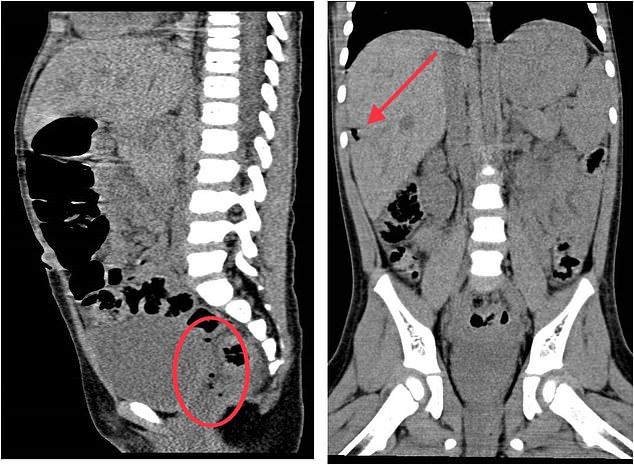

A girl's injuries from being impaled on a toy were so "unbelievable" that doctors thought she was a victim of child abuse, medics have revealed. Picture Shows: X-rays showing air bubbles near her rectum (left) and under the kidney (right), suggesting she had a rupture in her intestines